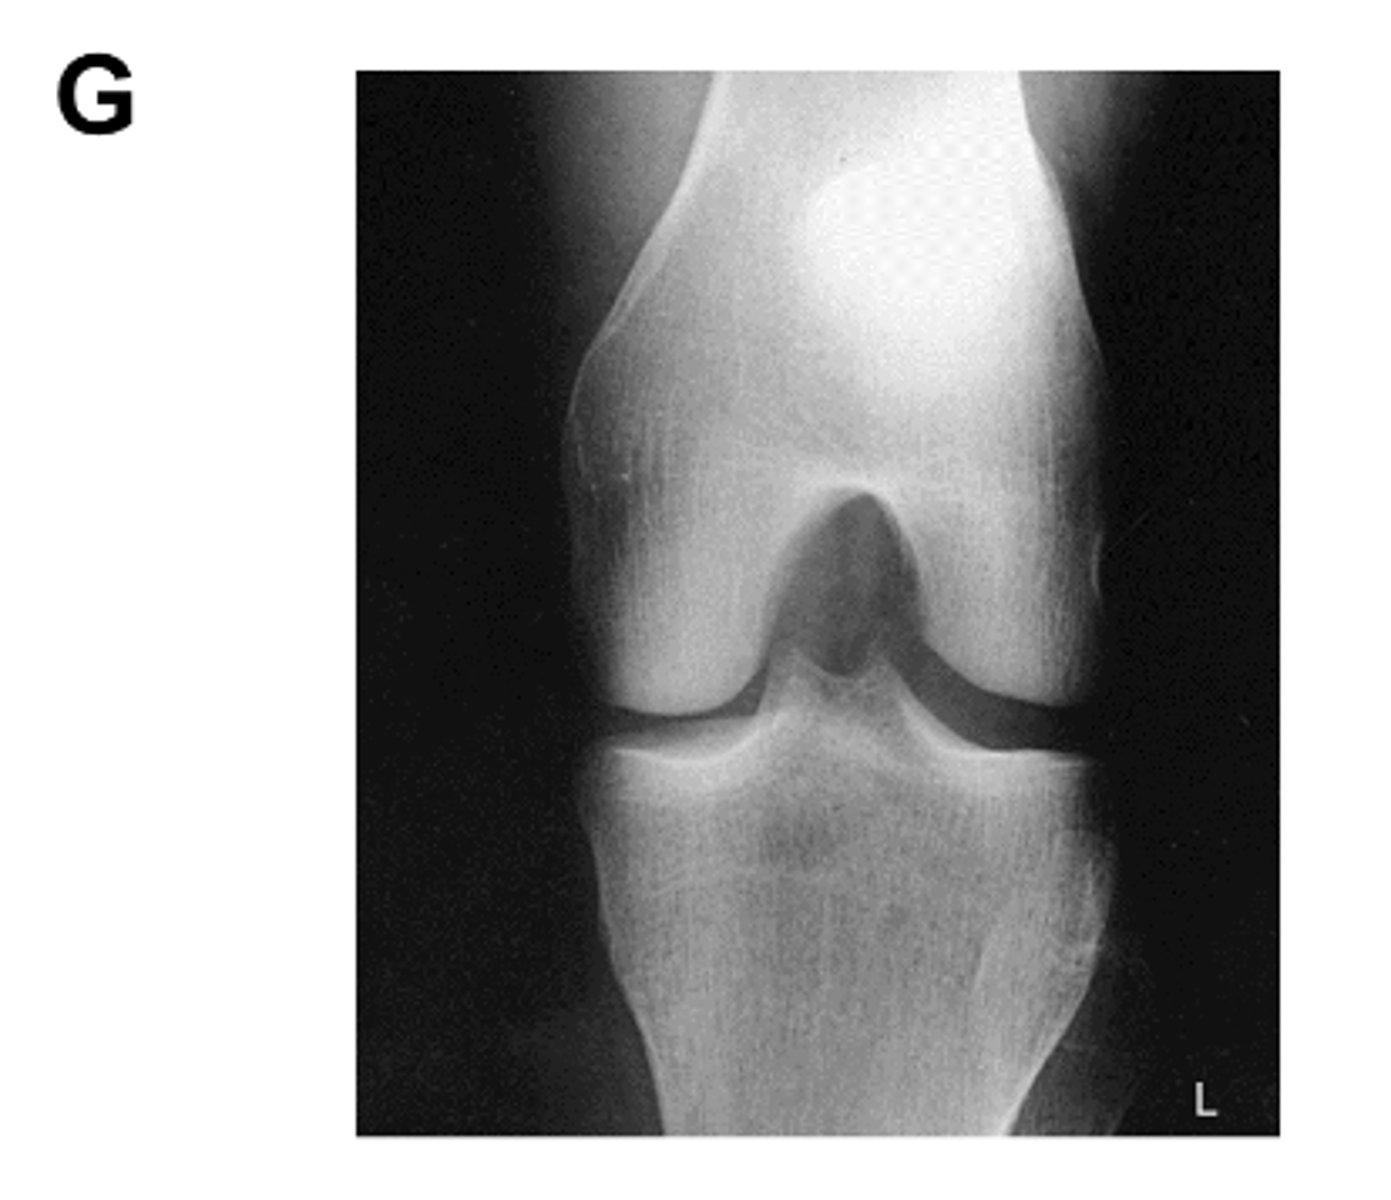

Identify the projection:

PA Axial Knee (Camp-Coventry Method)

intercondylar fossa